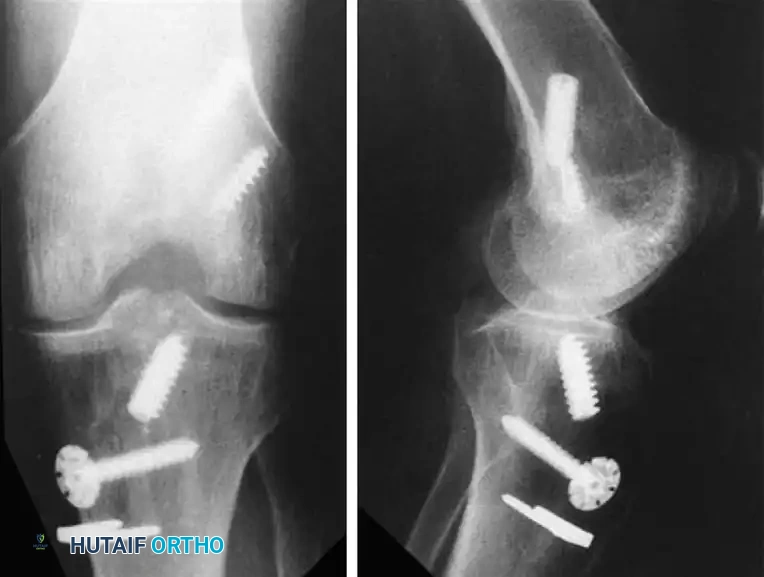

Associated Surgical & Radiographic Imaging

Hutaifortho's Orthopaedic Diagram